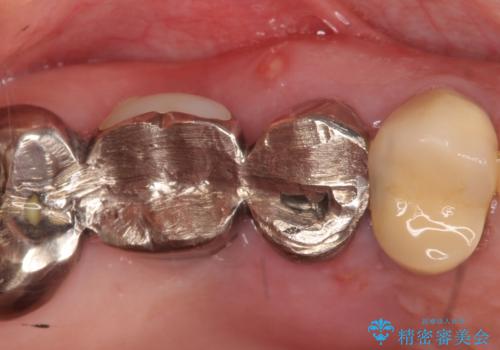

- 右上のブリッジでものを咬むと違和感があり、歯茎に膿の出口もできているので診て欲しいといらっしゃった方の症例です。

右上の567ブリッジを外したところ、右上5は歯根破折により保存不可能だったため、右上56部にインプラントを埋入し欠損補綴を行いました。